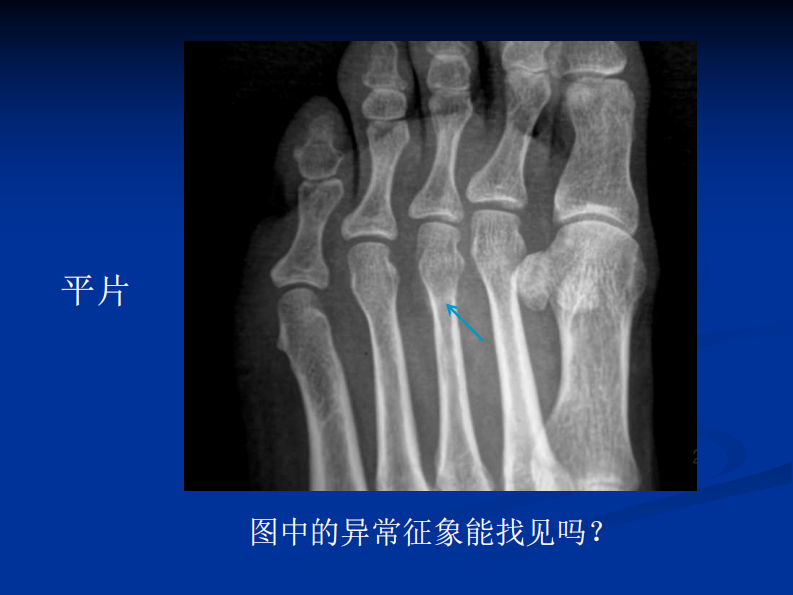

影像学病例读片-应力性骨折.pdf